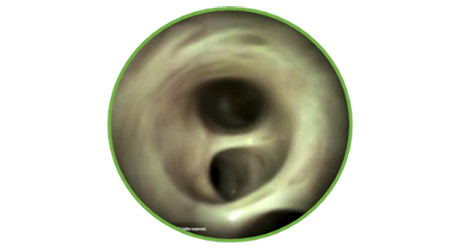

HabibTM EndoHBP hat einen Durchmesser von 8Fr (2,7 mm), 180 cm Länge und zwei Edelstahlelektroden an der distalen Spitze. Die Radiofrequenz Energie wird an beide Elektroden angelegt, um das umgebende Gewebe zu erwärmen.